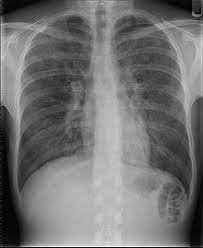

Versteckte lungenentzündung bei kindern. Meist hatten die Kinder einige Tage zuvor Fieber Husten und angeschwollene Schleimhäute im Bereich des Kehlkopfes und der Stimmbänder. Die kalte Lungenentzündung tritt häufiger bei Kindern als bei Erwachsenen auf da Kinder etwa in Kindergärten oder Schulen einer höheren Ansteckungsgefahr ausgesetzt sind. Eine kalte Lungenentzündung wird durch Tröpfcheninfektion Niesen Husten Sprechen von Mensch zu Mensch übertragen.

Auch wenn die Anzeichen je nach Alter und von Person zu Person unterschiedlich stark ausgeprägt sind zeigen sich diese Symptome bei der kalten Lungenentzündung jedoch am häufigsten. Nach zwei Monaten und bis zu fünf Jahren sind die Lungen des Babys am anfälligsten für Viren aber mit einer bakteriellen Infektion ist die Krankheit ziemlich schwierig. Eine typische durch Pneumokokken ausgelöste Lungenentzündung Pneumonie dagegen wäre wohl nicht zu übersehen.

Das Fieber steigt in Rekordgeschwindigkeit über 39 Grad die Atmung geht immer schneller und schmerzt die Kinder sind kraftlos und im Blutbild finden sich hohe Entzündungswerte. Es kann zu hohem Fieber und einer erhöhten Atemfrequenz kommen die gerade für eine Lungenentzündung bei Kindern typisch ist. Ursachen Eine Lungenentzündung bei Kindern kann als Folge einer anderen Atemwegserkrankung wie beispielsweise Asthma auftreten oder eine Komplikation anderer Erkrankungen zum Beispiel Mukoviszidose sein.

Oft kommt es auch zu Hauteinziehungen des Brustkorbs Übelkeit und Ohrenschmerzen. Versteckte Lungenentzündung bei Kindern ist ziemlich seltenPhänomen.